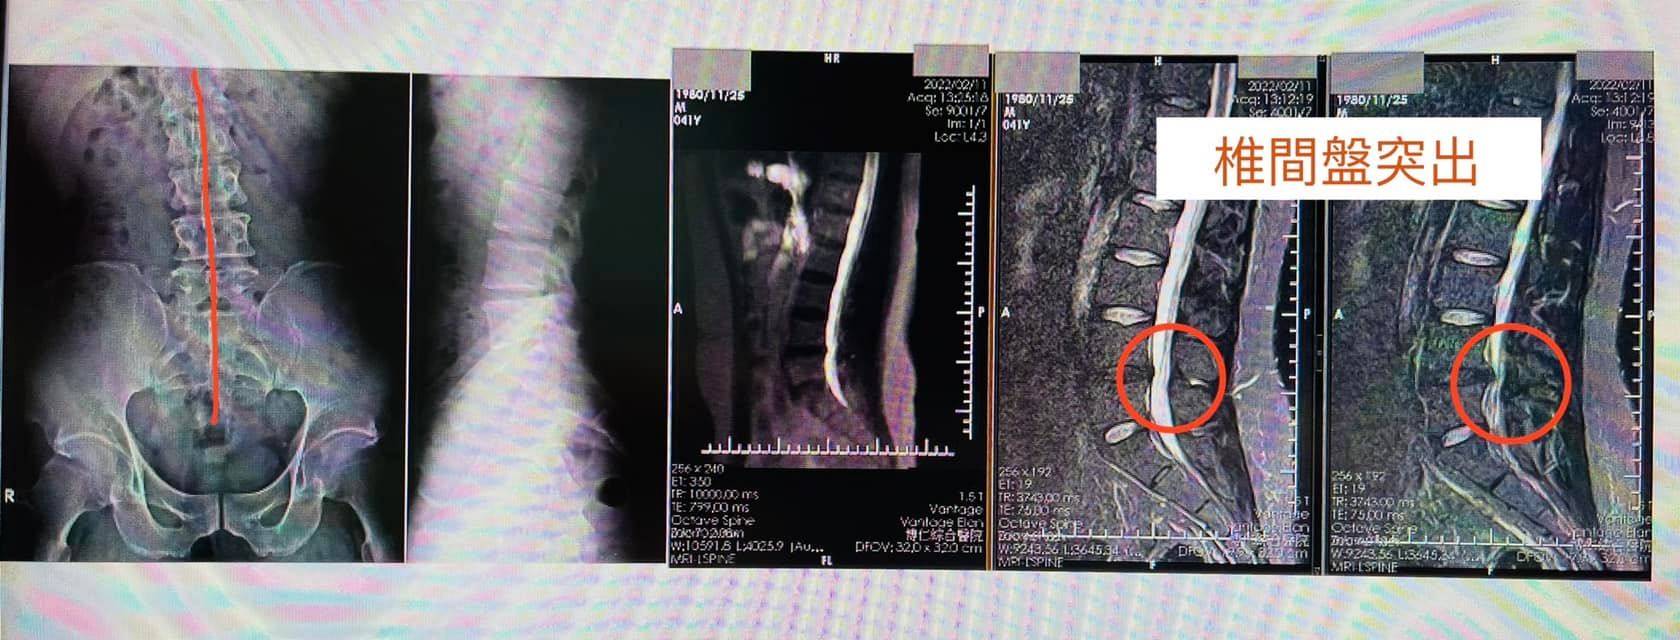

✅拍攝MRI 診斷:

1.左側L 4L5椎間盤突出

2.輕微脊椎側彎

3.梨狀肌症候群